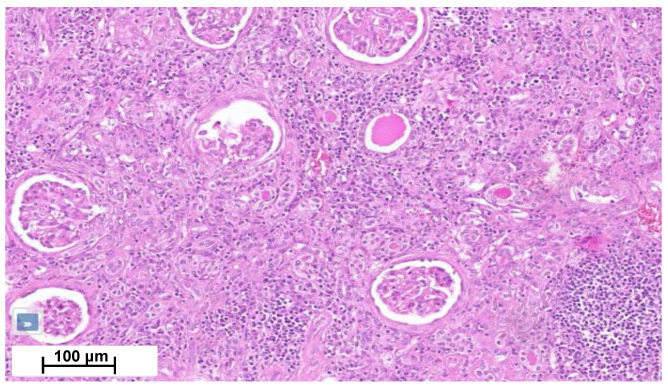

Four months later, a second episode of acute kidney injury occurred (plasma creatinine reaching 7.8 mg/dL; eGFR 7 mL/min/1.73 m2). His urine samples showed a fluctuating albuminuria (0.5 to 1 g/g of urine creatinine), leukocyturia without cast formation, and microscopic hematuria without acanthocytes. In the absence of a clear diagnosis, the nephrology team performed a biopsy of his solitary right kidney. Renal biopsy showed an interstitial nephritis with lymphocyte infiltration without glomerular change (Figure 4). Immunofluorescence was unremarkable. Electron microscopy was not performed. Ziehl and Grocott staining were negative. Infectious work-up failed to detect tuberculosis (normal interferon-gamma release assays (IGRAs) and Mantoux tuberculin skin test for Mycobacterium tuberculosis (MBT), MBT PCR, and 3-week MBT cultures of urine samples). Also, ELISA assays for Brucella spp., Bartonella henselae, Schistosoma mansoni, human immunodeficiency virus and Burkholderia pseudomallei were negative. Antineutrophil cytoplasmic antibodies, antinuclear antibodies, angiotensin-converting enzyme and protein electrophoresis were normal, as well as IgG4 level (Table 1). Ophthalmological work-up was normal.

Bladder biopsies were later obtained and showed a fibrous tissue with numerous non-necrotic granulomas and multinucleated giant cells (Figure 2D). Special PAS and Zhiel staining did not reveal any pathogens. No coating nor malignancy was observed.